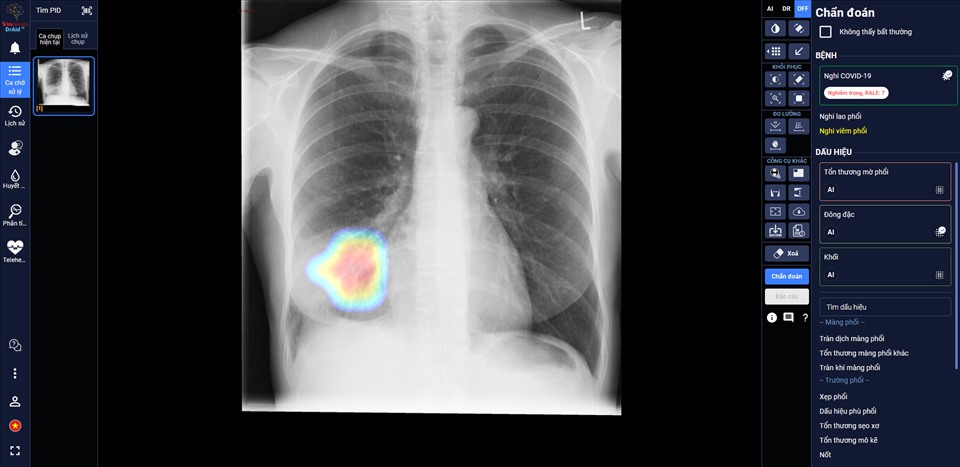

DrAid giúp bác sĩ theo dõi mức độ tổn thương phổi ở một bệnh nhân F0 trên ảnh X-quang phổi. Nguồn: laodong.vn |

Theo đánh giá của các bác sĩ tại Trung Tâm Y Tế Kỳ Anh – Hà Tĩnh, AI đã giúp đỡ các bác sĩ theo dõi tổn thương của bệnh nhân qua các ngày, nhận diện rõ ràng là tổn thương lan rộng như thế nào,nhận diện các tổn thương nhỏ dễ bỏ sót.